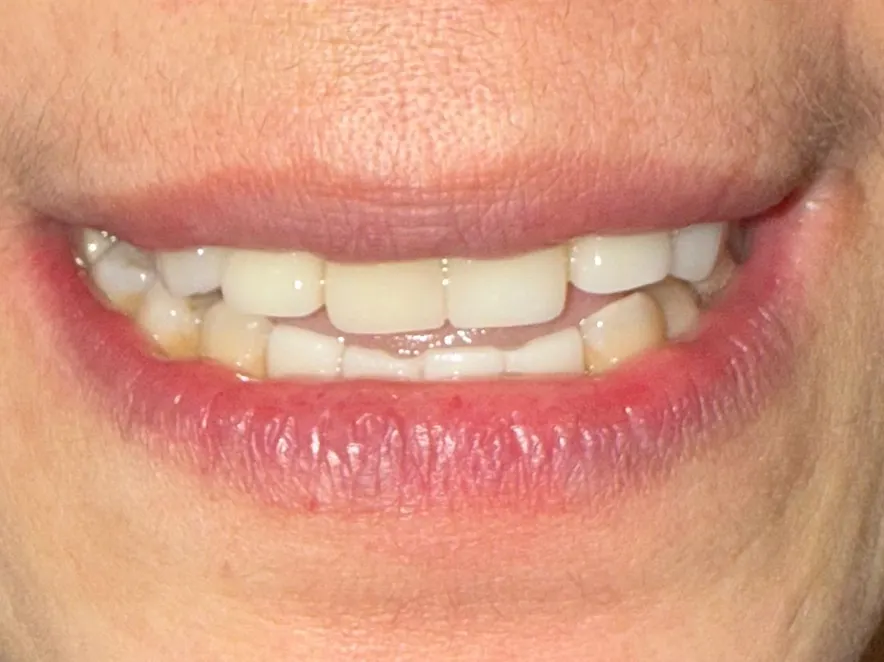

At MC Dental Glen Waverley, Dr Joe recently completed a patient’s smile transformation. He carefully worked through a tailored treatment plan that restored health, improved function, and gave the patient back their smile, plus their confidence! (Photos shown below)

Many patients come to us with multiple dental concerns that require a stepped approach to treatment. A single patient’s journey may involve a combination of fillings, root canal therapy, periodontal (gum) treatment, veneers, crowns or bridges, and sometimes even implants. Every case is different, and that’s why our team takes the time to plan each stage carefully, working with you to prioritise comfort, function, and results.